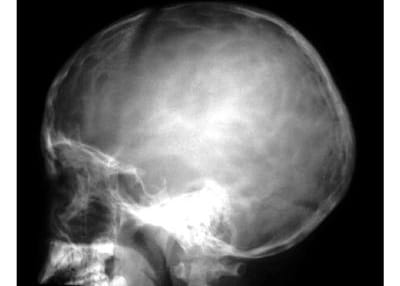

骨质疏松:指一定单位体积内正常钙化的骨组织减少,即骨组织的有机成分和钙盐都减少,但骨内有机成分和钙盐含量比例仍正常,x 线表现主要为骨密度减低,骨小梁变细、减少、间隙增宽,骨皮质出现分层和变薄现象。疏松的骨骼易发生骨折。

骨质增生硬化:是一定单位体积内骨量的增多,x线表现为骨质密度增高。伴或不伴有骨骼的增大,骨小梁增粗、增多、密集、骨皮质增厚、致密。